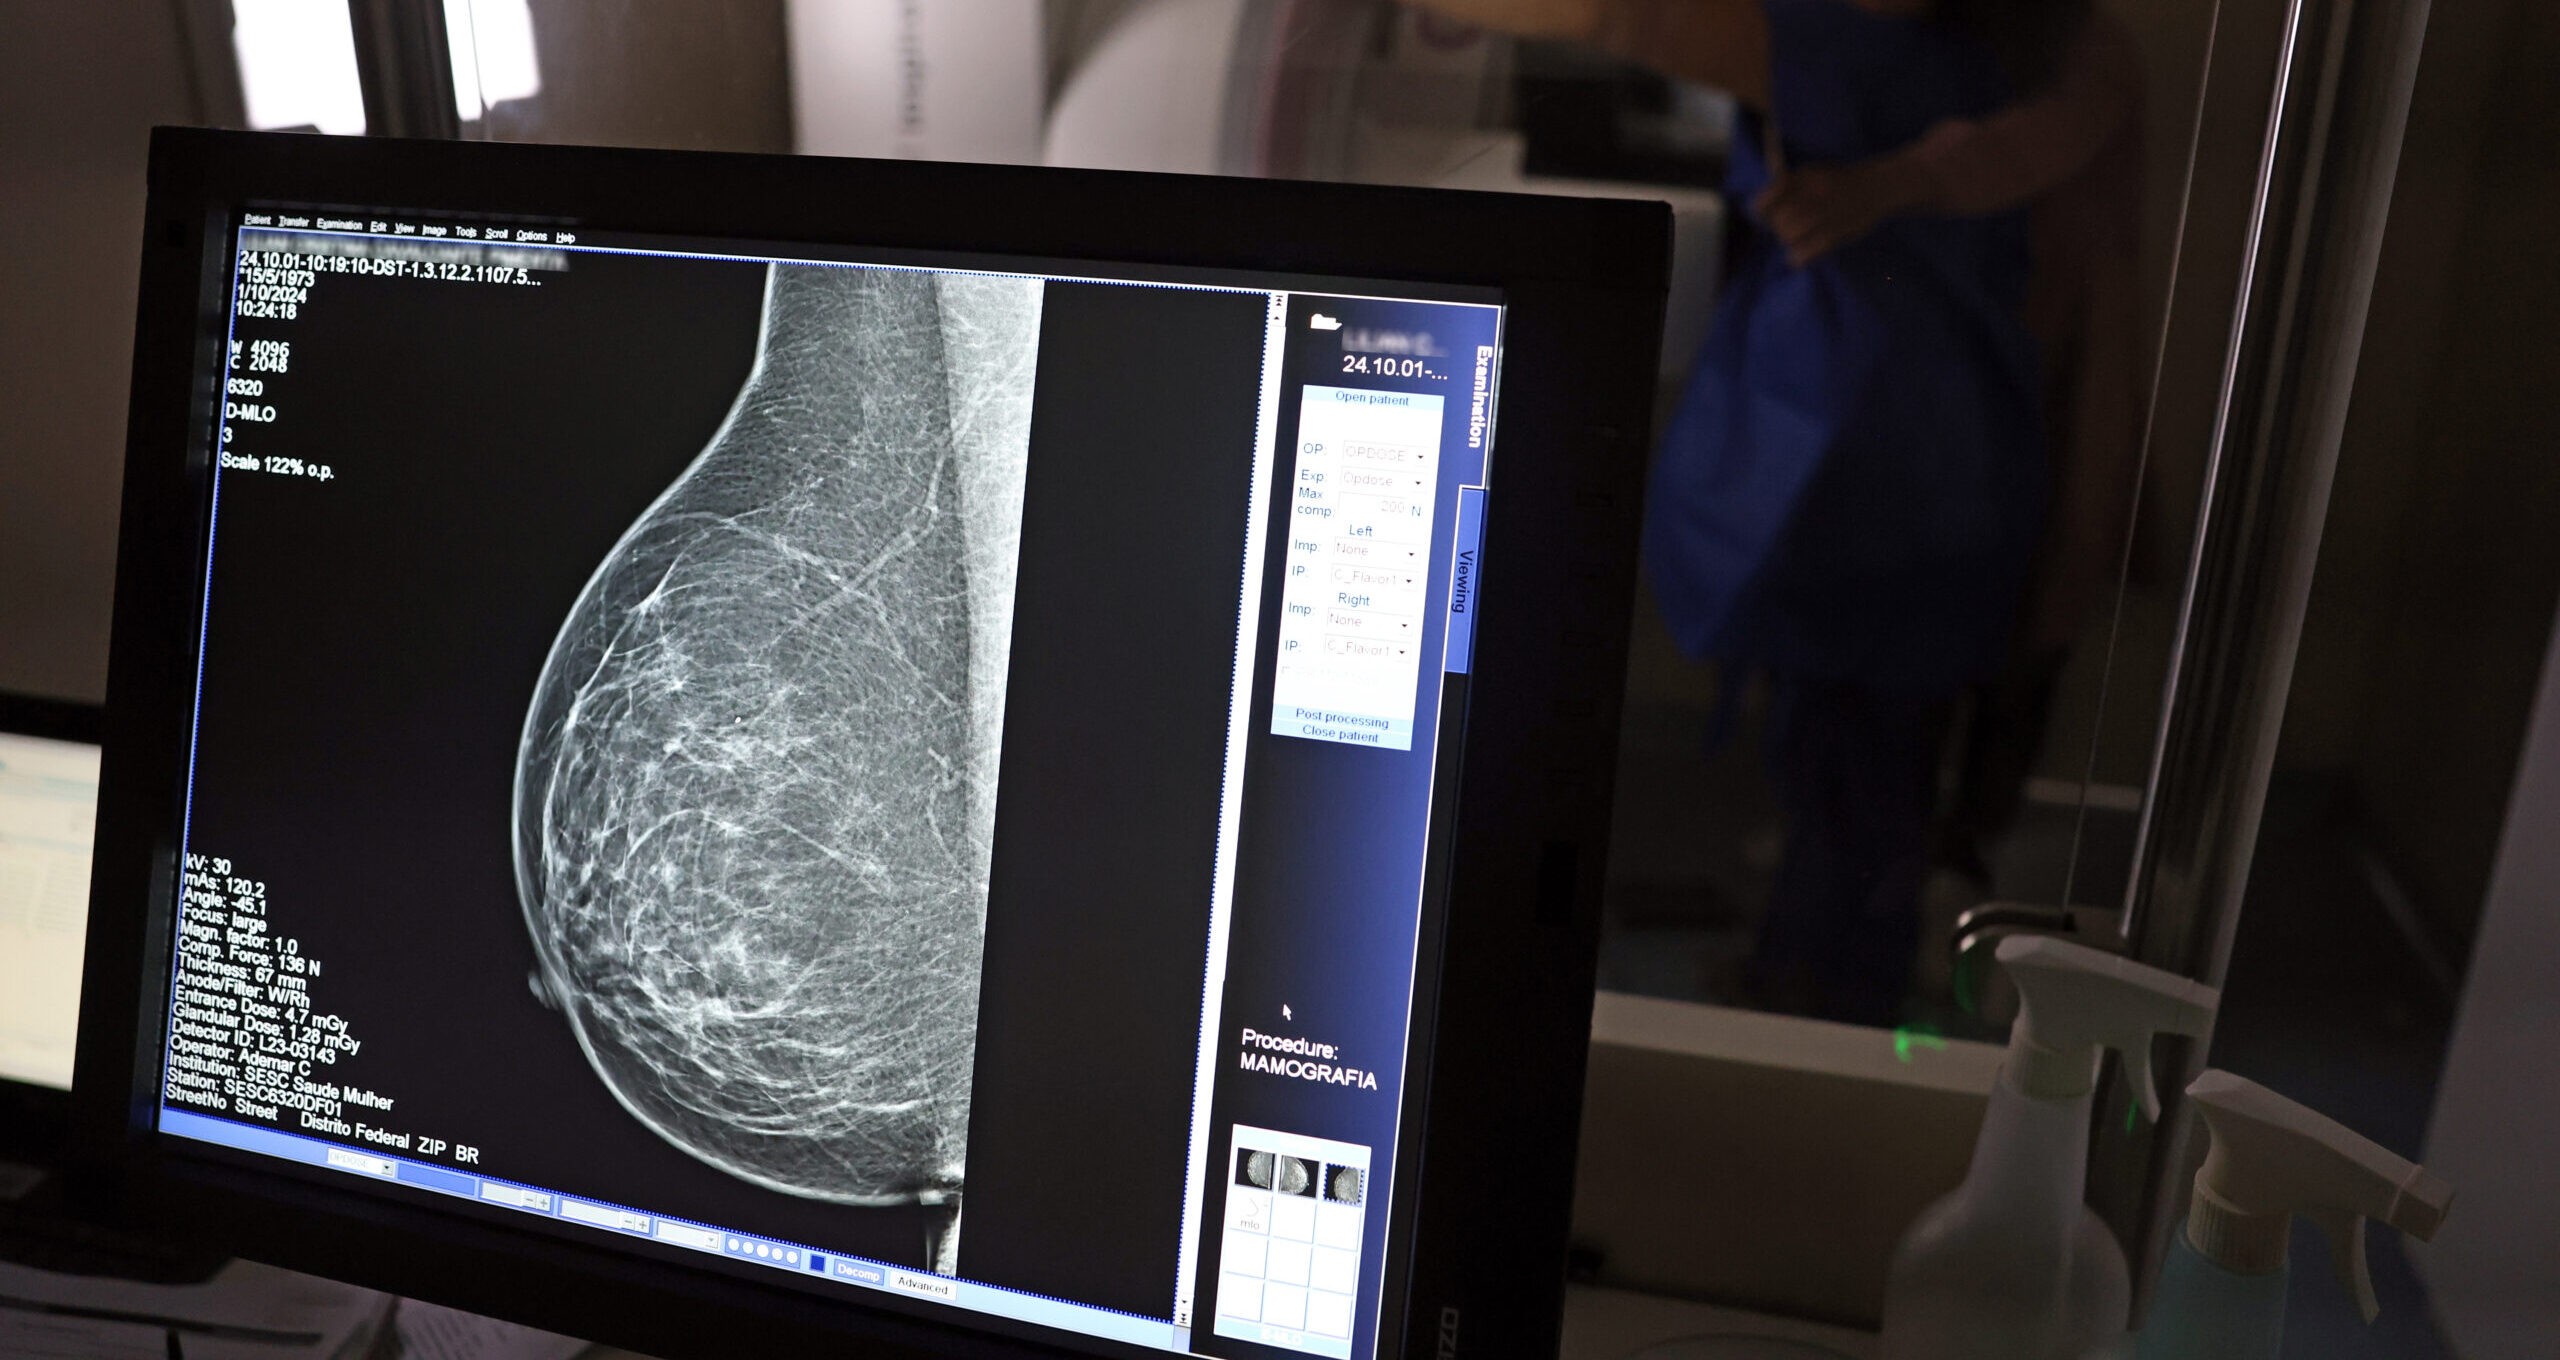

Caminhões da Mamografia farão mais de 5 mil exames em janeiro; veja o cronograma

Caminhões da Mamografia farão mais de 5 mil exames em janeiro; veja o cronograma

Caminhões da Mamografia percorrerão os municípios piauienses. Ascom Sesapi Os Caminhões da Mamografia vão percorrer diversos municípios